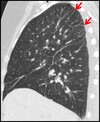

1

Not at all

2